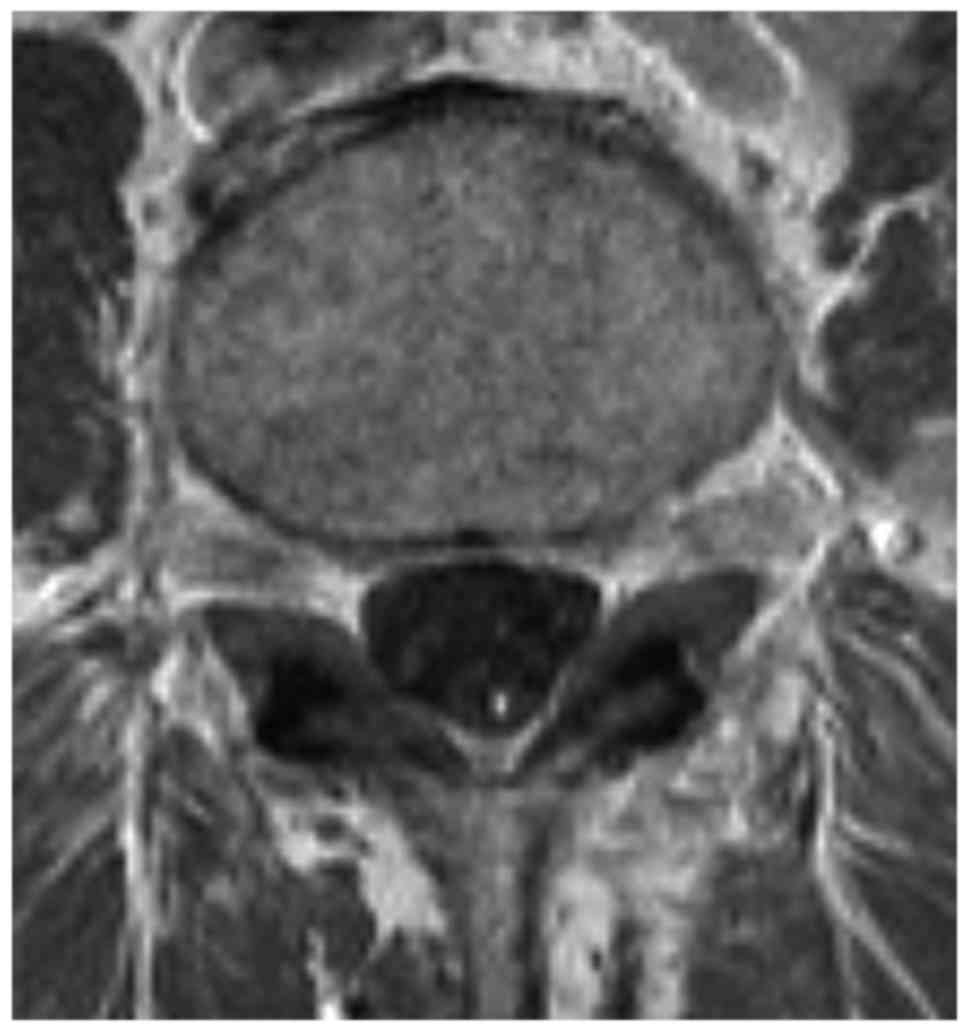

Magnetic resonance imaging MRI scan is essential to rule out cauda equina as no single or collective features will definitely confirm or exclude diagnosis. An MRI scan should either be performed on an urgent basis or an emergency basis depending upon the clinical situation. By contrast a cross sectional MRI view at L5S1 in a patient without cauda equina syndrome showing an unobstructed vertebral canal arrows from top down.

The presence or absence of cauda equina impingement was determined on MR imaging. Of a patient with cauda equina syndrome showing a large irregular disc herniation arrow occupying most of the vertebral canal.